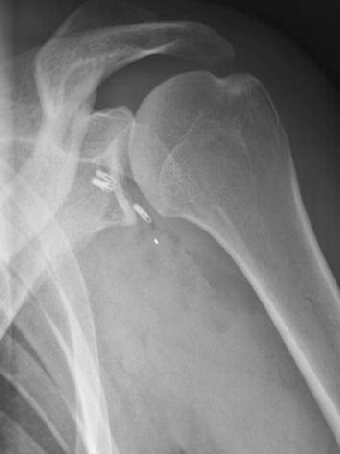

X-Ray was normal.

MRI revealed SLAP tear and labral tear with Supraspinatus fossae cyst pressing on the Suprascapular Nerve.